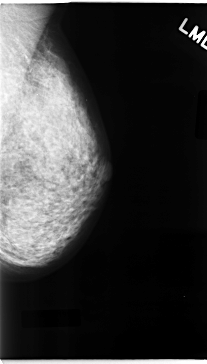

C_0092_1.LEFT_MLO

LEFT_MLO LINES 4728 PIXELS_PER_LINE 2688 BITS_PER_PIXEL 12 RESOLUTION 50 NON_OVERLAY